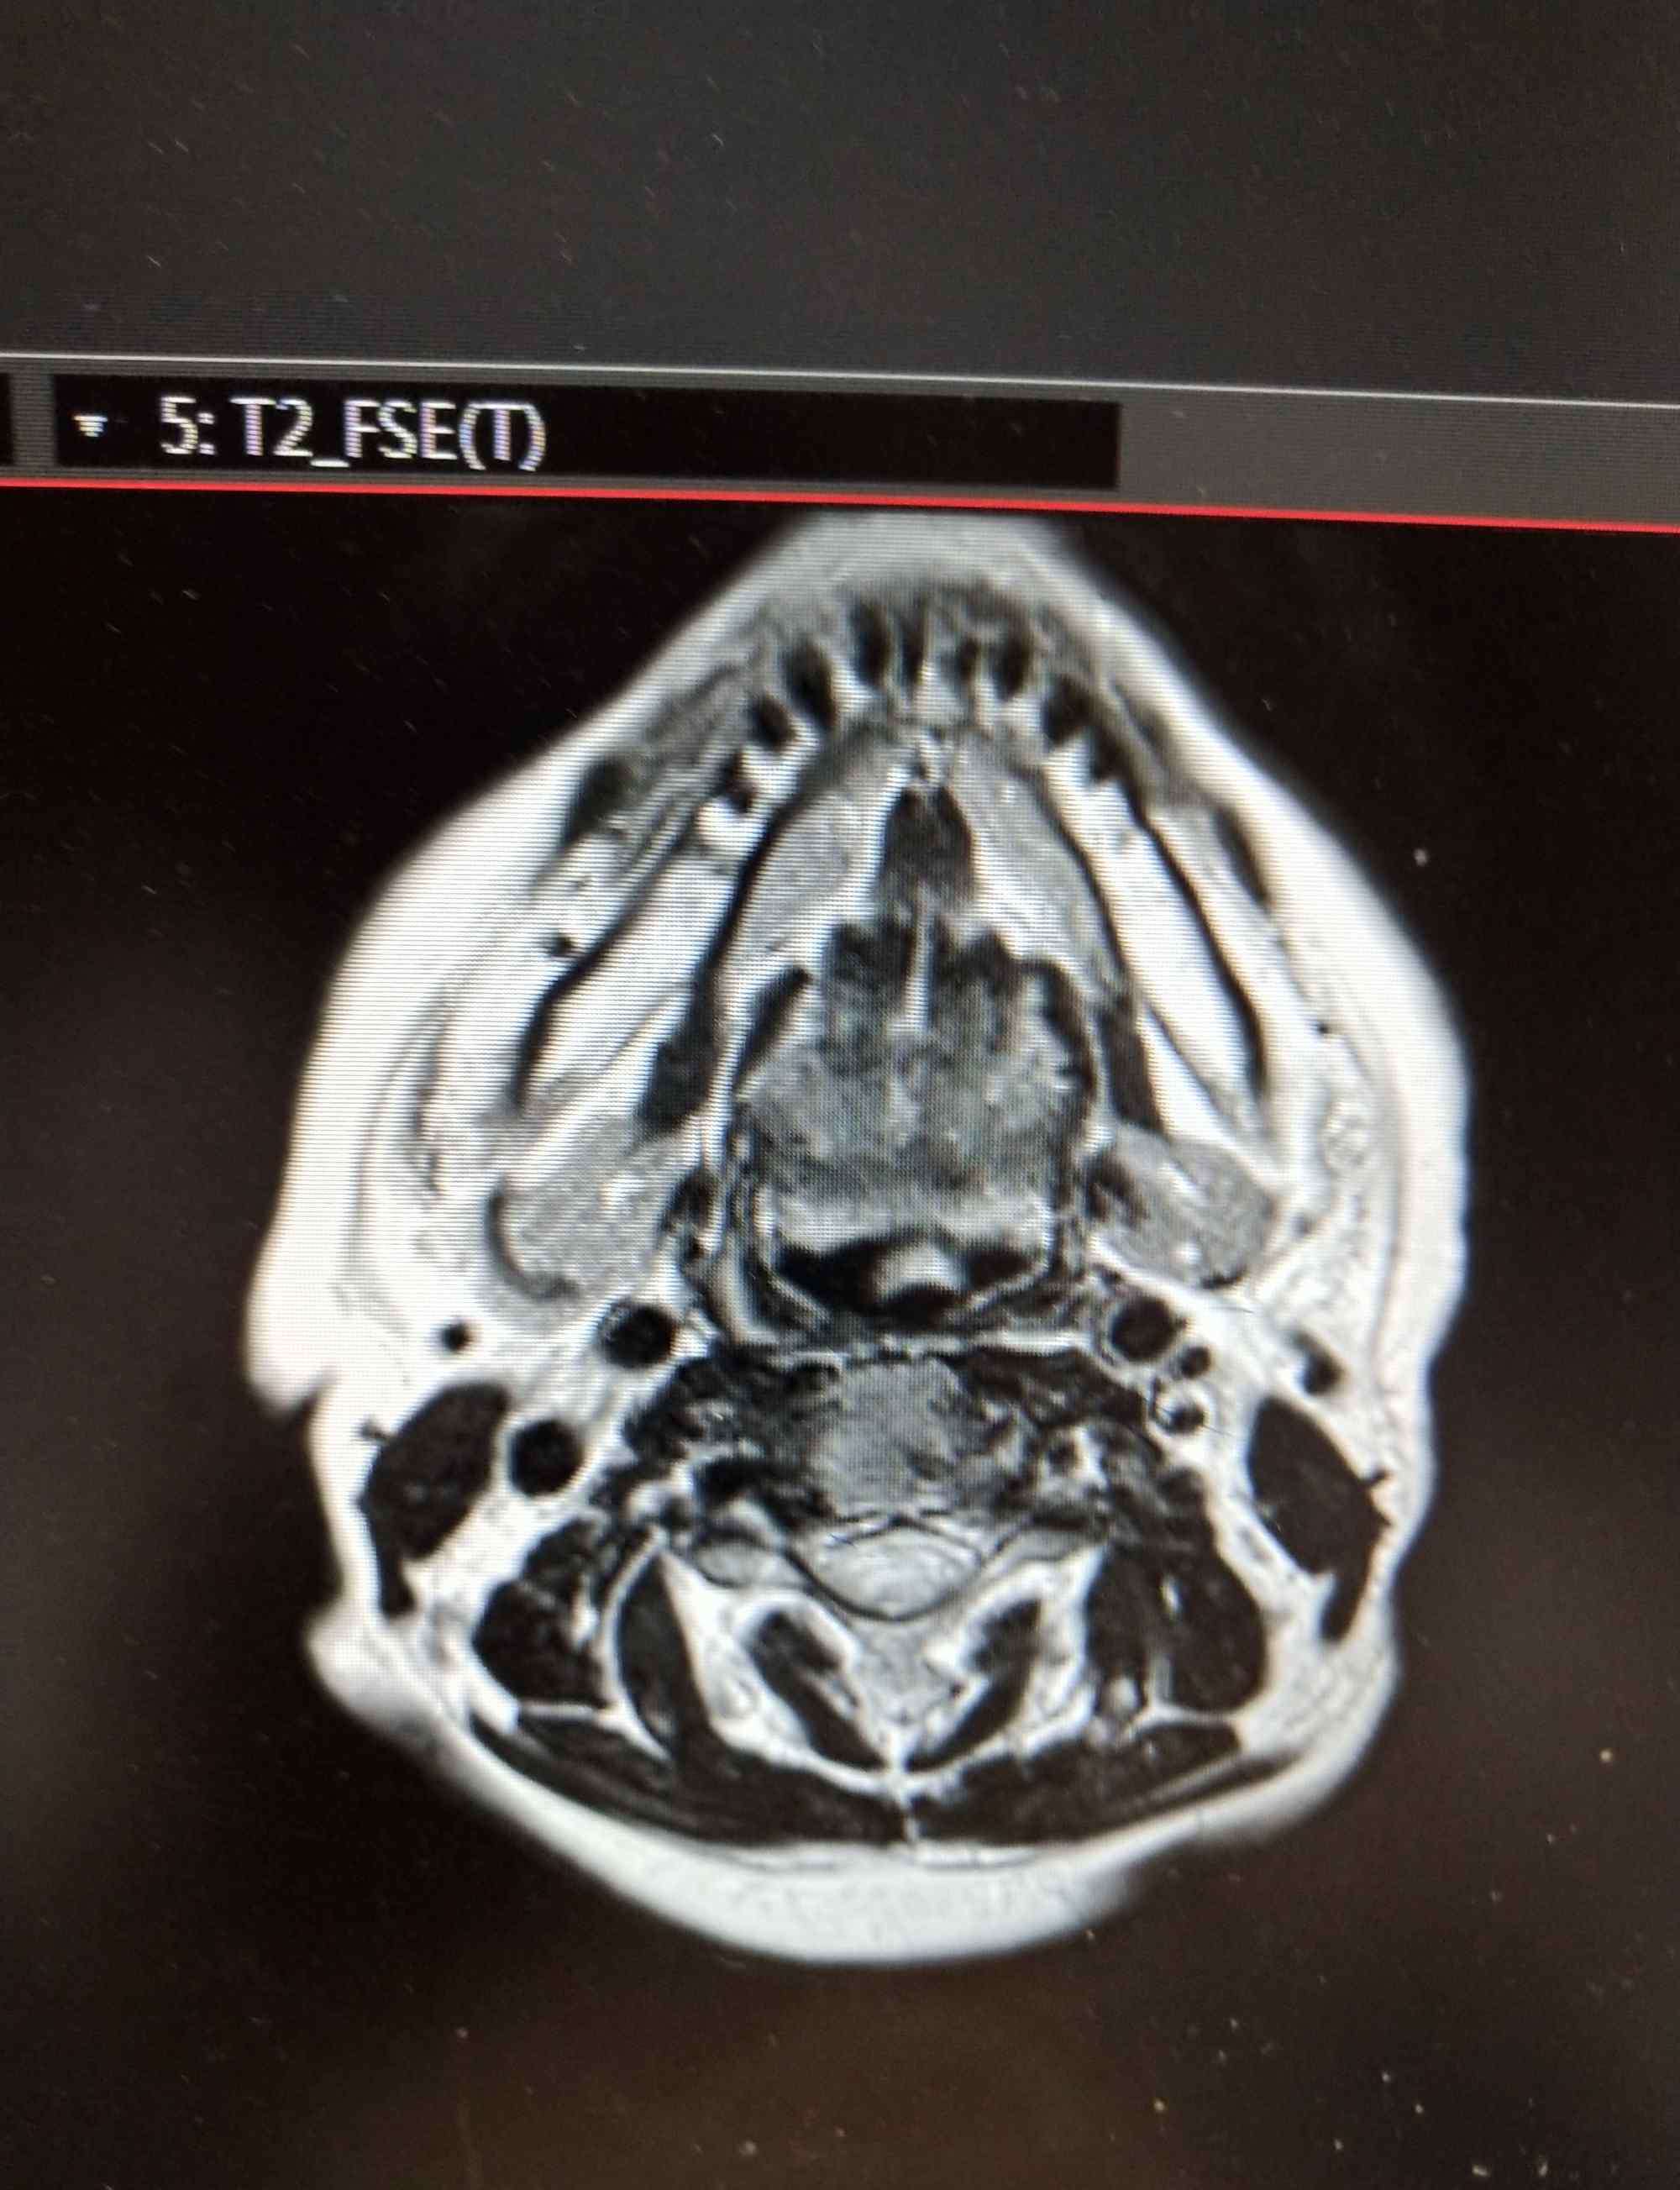

MRI